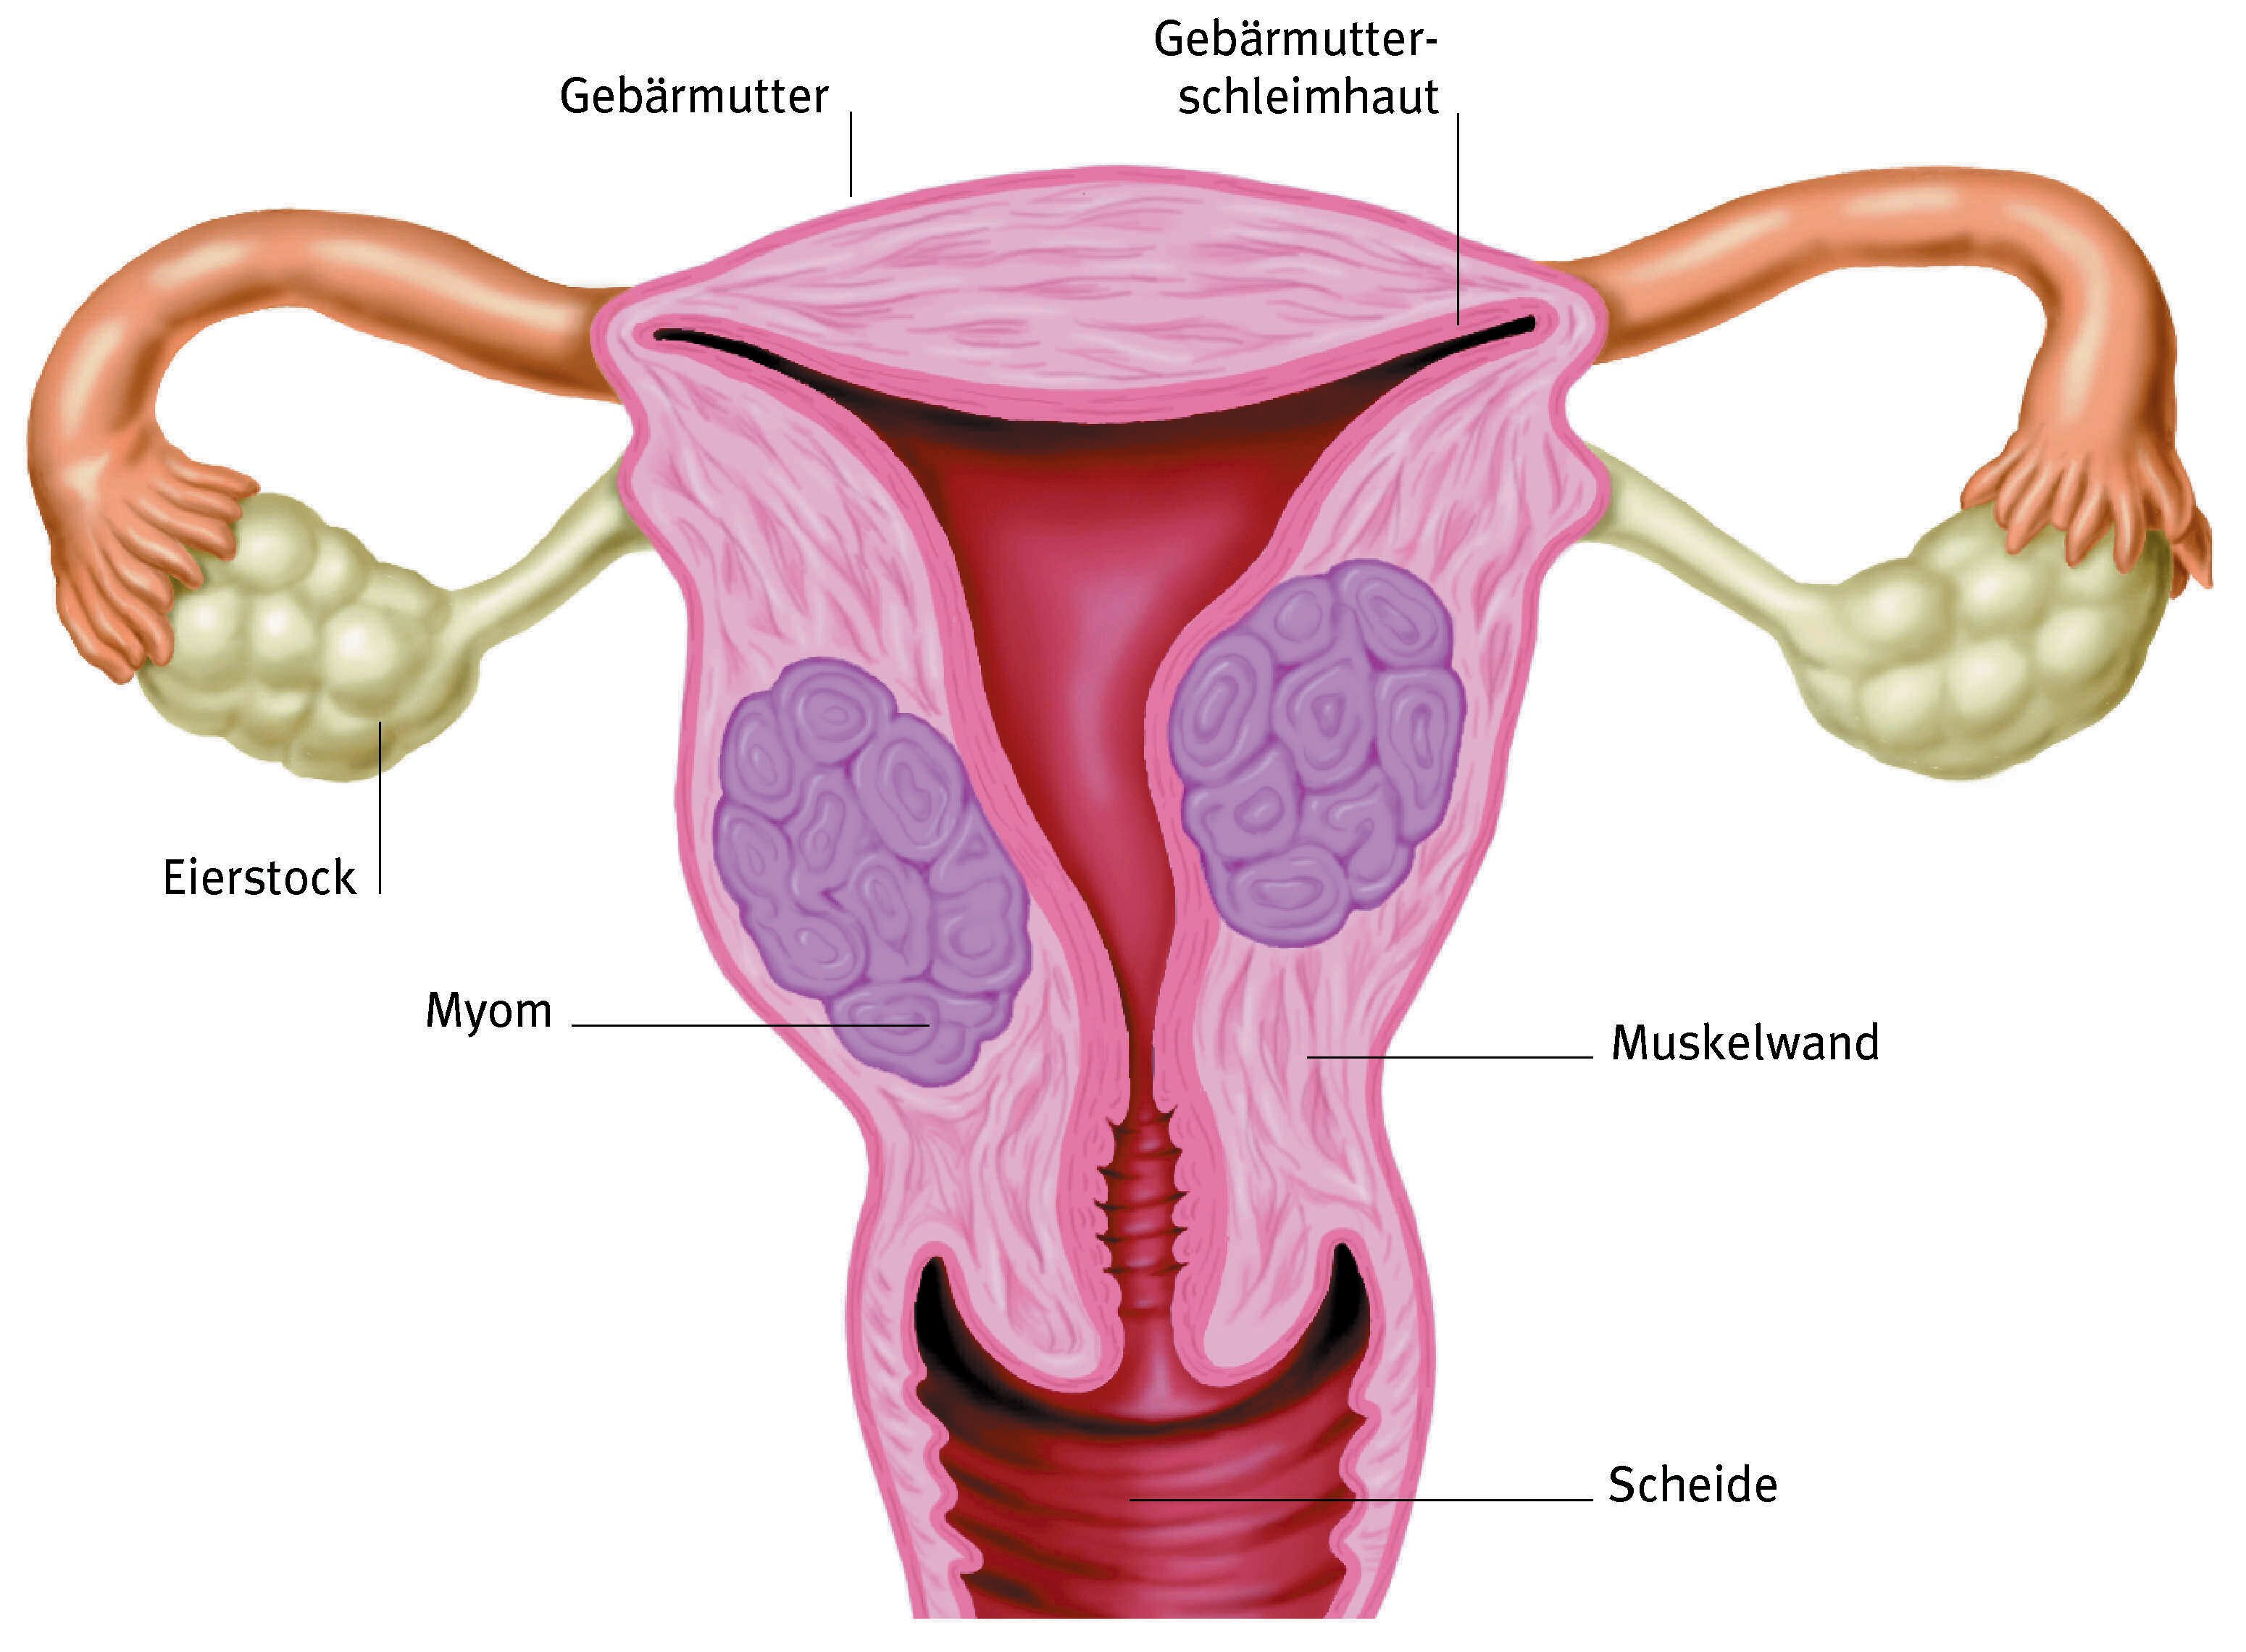

Qu’est-ce qu’un myome ? Un myome est une tumeur qui se développe le plus souvent à l’intérieur ou à l’extérieur de l’utérus et désignée par le nom plus familier de fibrome..

Un « fibrome » de l'uterus encore appelé par les médecins Myome, est une tumeur bénigne faite de la prolifération de cellules musculaires issues de la paroi de l’utérus, cela à -un.

Pourquoi le myome apparaît-il ? Le myome résulte de la prolifération des cellules musculaires de l’utérus. S’il n’existe pas de cause déterminée, le myome est.

Définition. Un myome ou fibrome est une tumeur bénigne se développant à partir de tissu musculaire et de tissu fibreux. La dégénérescence cancéreuse est.

Le myome est appelé une tumeur bénigne, qui se développe dans les tissus de l'utérus. La tumeur est semblable à la spire noueuse et peut être localisée à la fois sur.

Un myome, communément appelé fibrome, est une tumeur bénigne (non cancéreuse) qui se développe dans ou autour de l’utérus. Les fibromes sont connus sous le nom médical.

Qu'est-ce qu'un myome ? Le myome, ou fibrome, utérin est une tumeur bénigne de l'utérus qui se développe au sein du muscle lisse. Il n'y a pas de risque que cette.